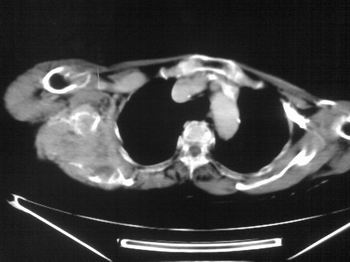

以下是引用zhangxu5888在2007-9-11 16:25:00的发言:[br]有侧肩胛骨溶骨性破坏且见软组织成分,增强软组织强化明显,中央见低密度坏死区!根据病史10年,考虑良性肿瘤恶性变!性质待定!

以下是引用老爱克斯新网客在2007-9-11 18:22:00的发言:[br]应该是良性肿瘤恶变,但因晚期破坏严重不能见到原来肿瘤征象无法判断,